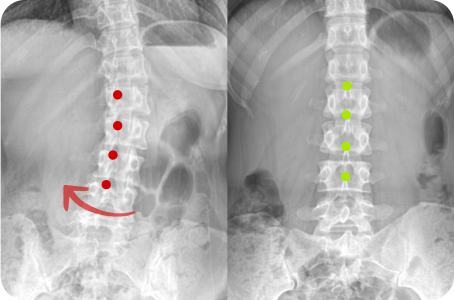

3차원 척추교정이란?

척추의 틀어진 방향과 휘어진 각도는 사람마다 모두 다릅니다.

옆, 앞, 뒤가 각자 틀어지고 꼬인 척추의 변형은 각도와 방향 모두를 고려한

3차원 척추 교정으로 바로잡아야 합니다.

정면, 측면 시각에서 틀어진 방향

척추 만곡의 각도

척추뼈 마디의 회전 변형